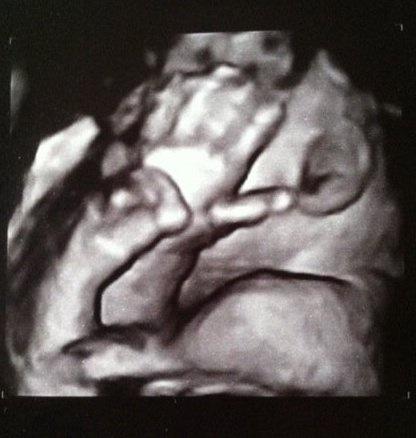

noch eein bildchen, wollte uns aber wieder nicht das gesicht zeigen :)